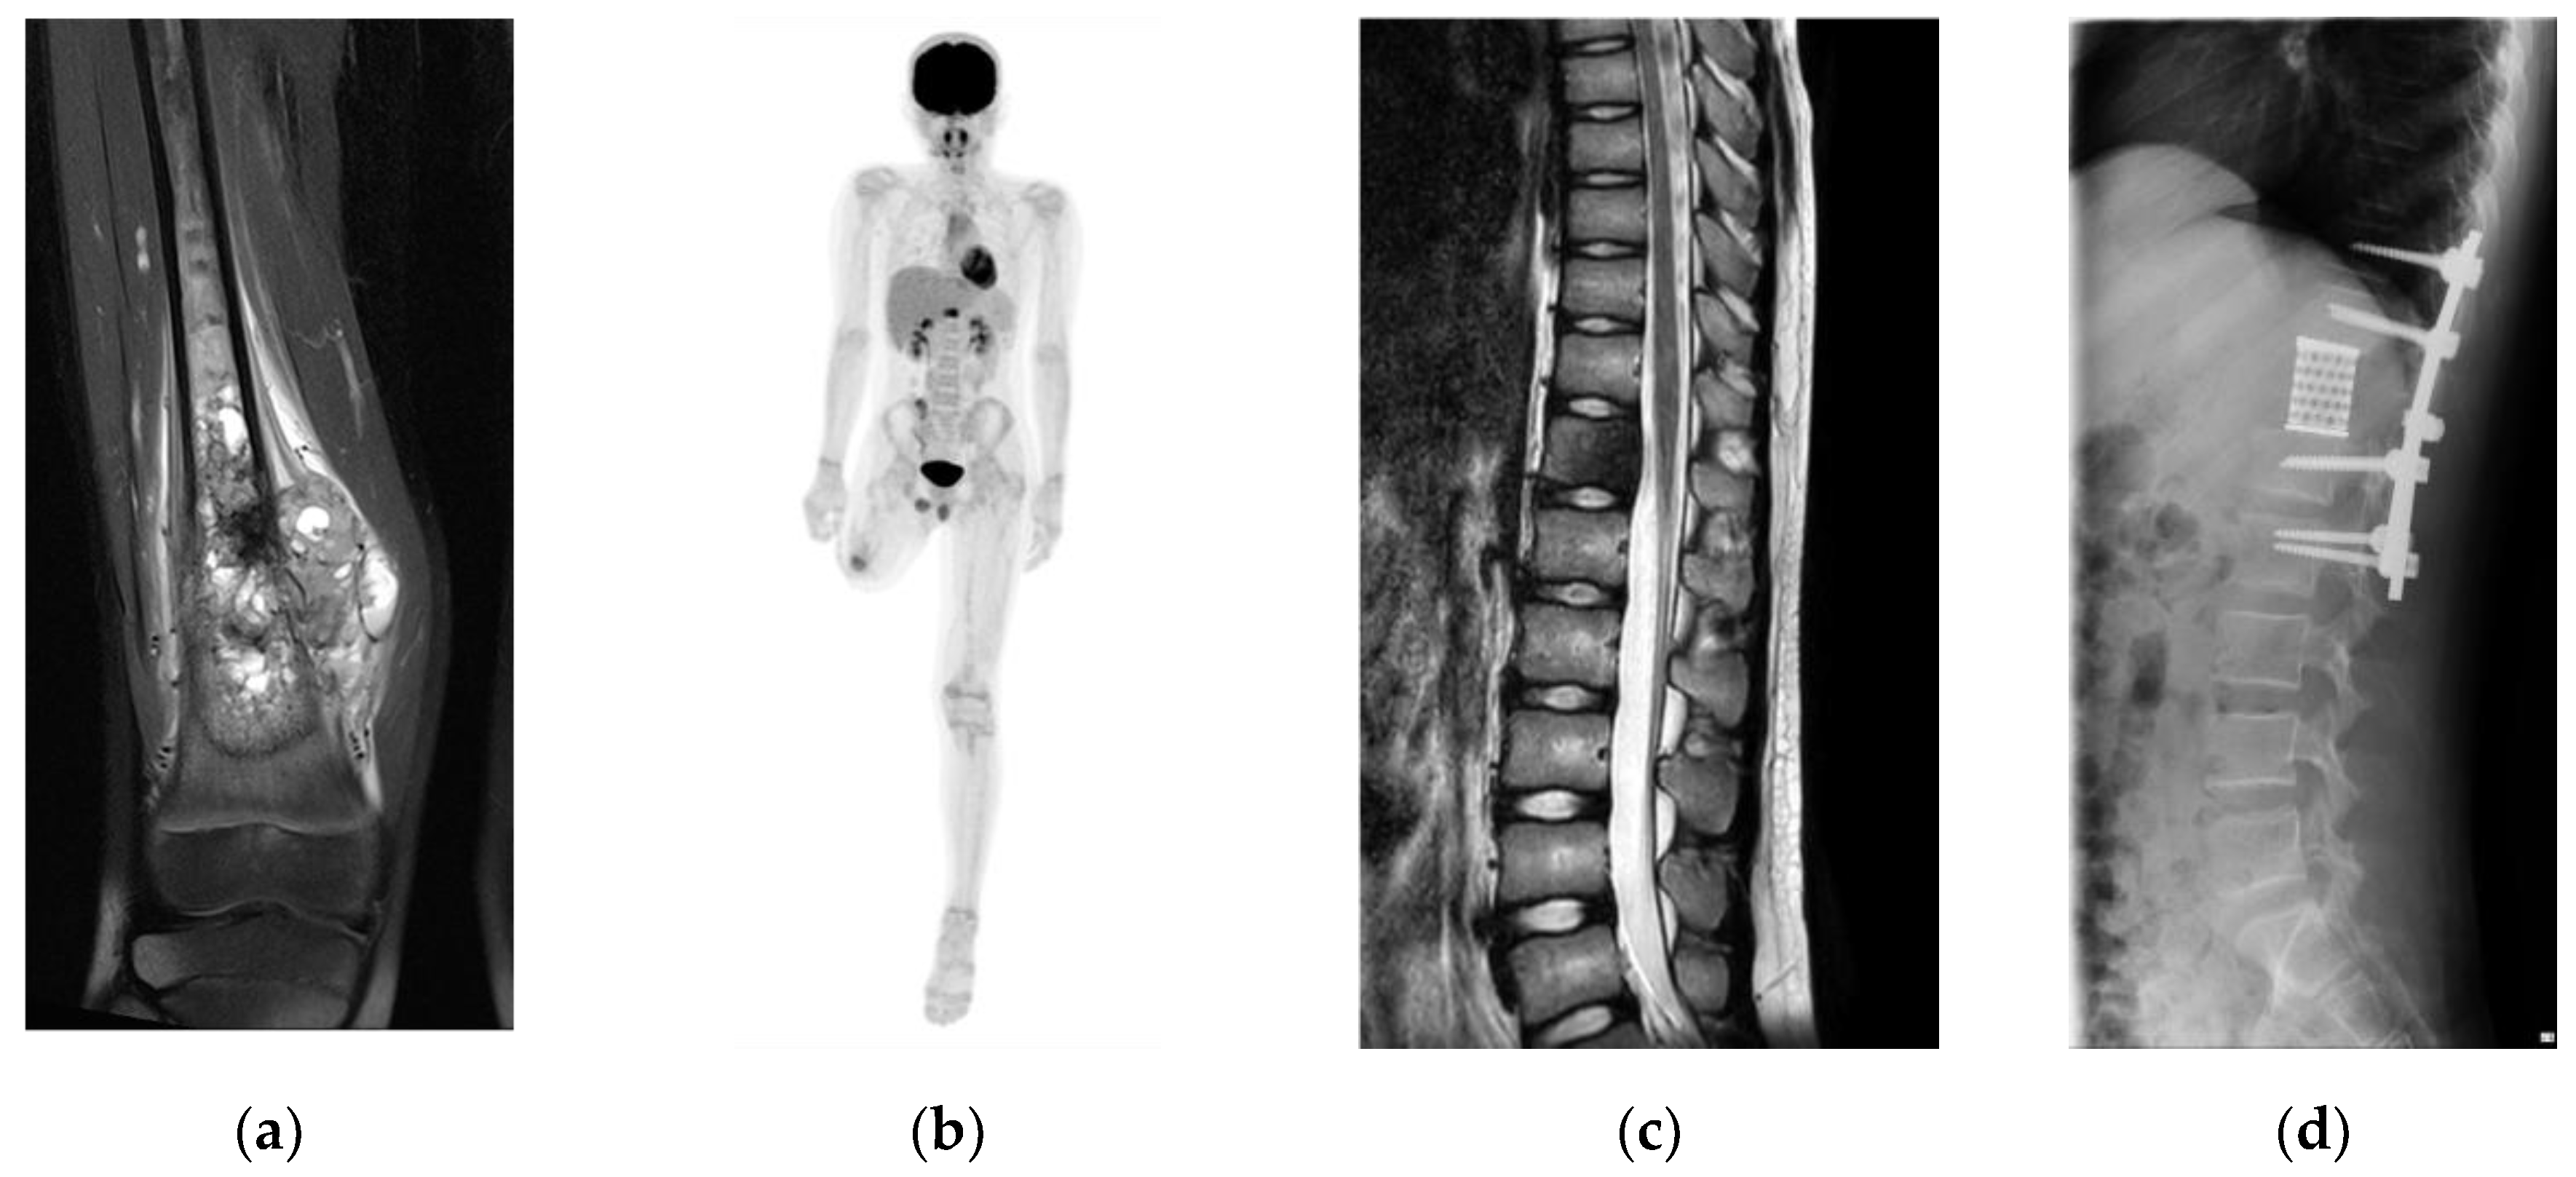

A 10-year-old boy was diagnosed with conventional osteosarcoma of the right distal femur. The patient underwent perioperative chemotherapy with tumor resection. Three years later, the patient underwent above-knee amputation due to recurrence at the surgical site. Seven months later, a solitary metastasis in the 12th thoracic spine was pointed at 14-years-old. To achieve a disease-free status and prevent possible invasion of the spinal canal, second-generation TES was planned (Figure 2).

Figure 2. Clinical course of a 10-year-old male with conventional osteosarcoma. (a) Image of the primary lesion (right proximal femur, short τ inversion recovery). (b) Positron emission tomography shows a single metastasis in the 12th thoracic spine. (c) Sagittal image of the spine (T2-weighted image) and (d) after surgical resection of the 12th thoracic spine and reconstruction.